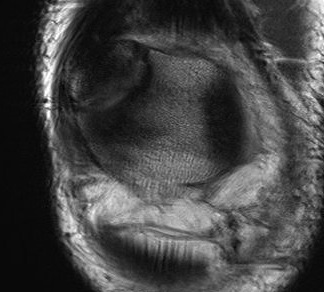

MRI